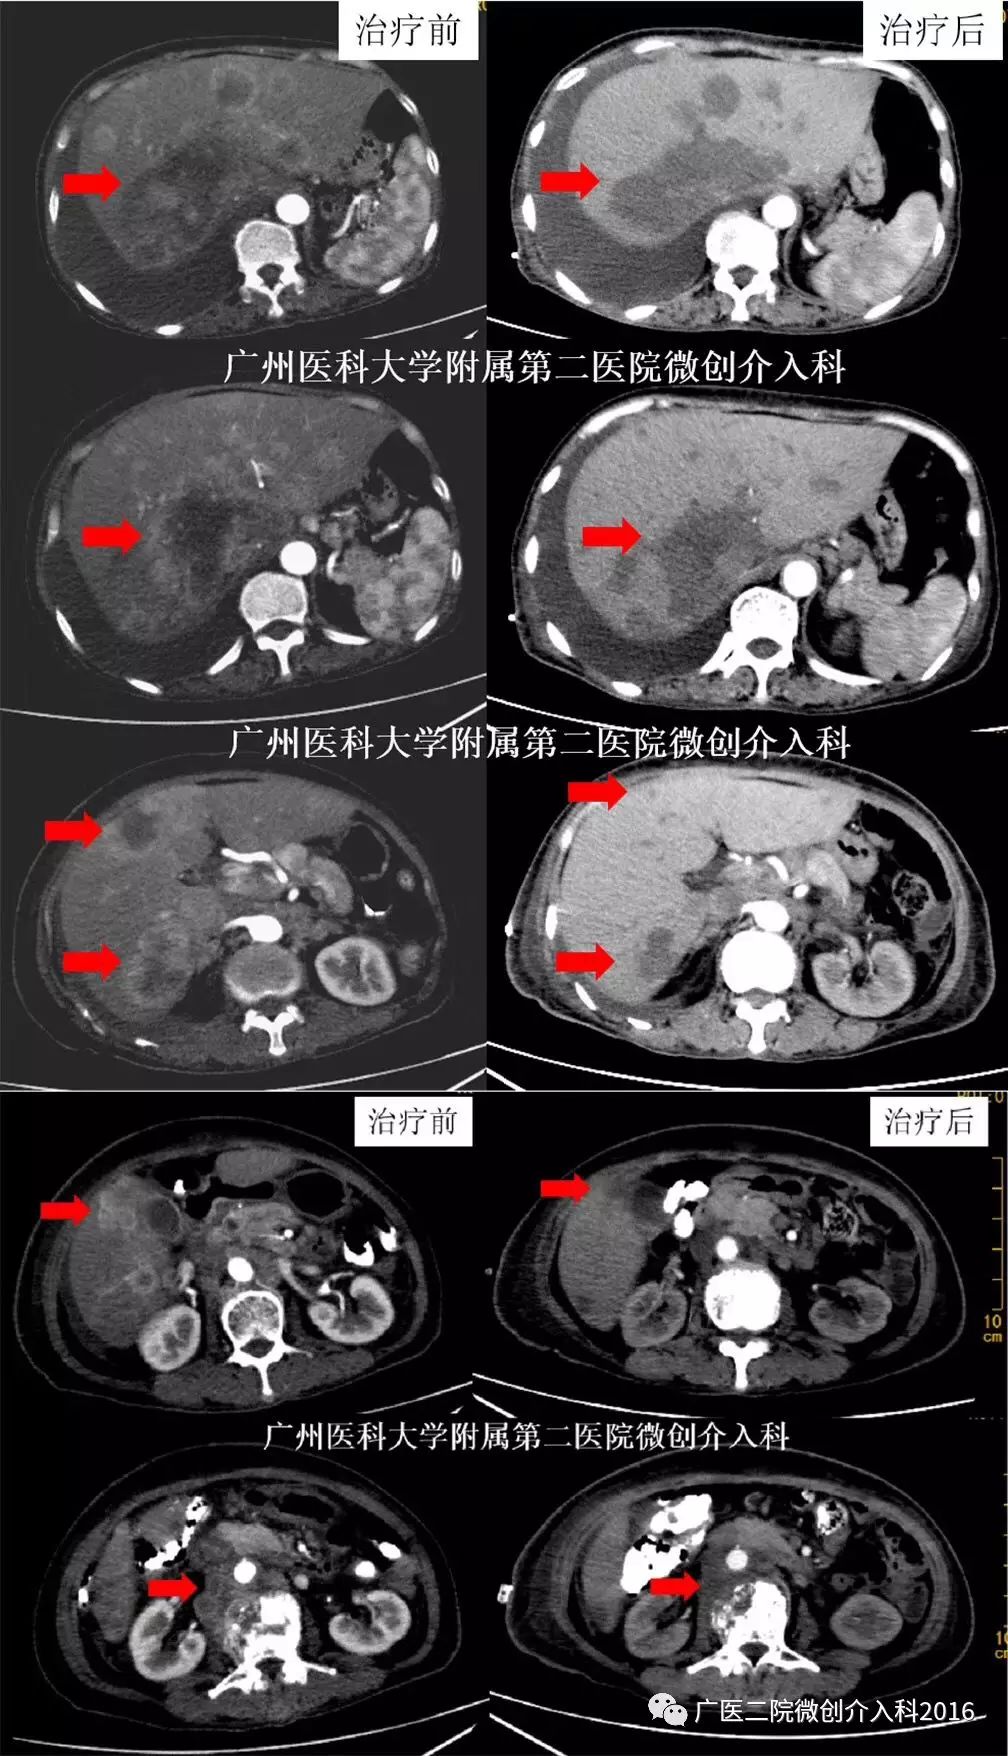

女性,66岁,胆管细胞癌并肝内、肾上腺、腹膜后、腰3椎体、双肺多发转移瘤,转辗多个医院治疗,但病情不断进展,为进一步治疗到我科就诊。经我科微创介入治疗(载药微球栓塞、动脉灌注化疗)联合靶向治疗、pd1免疫治疗,2个月后肝内、肾上腺、腹膜后多发转移瘤病灶明显坏死、缩小、消失,效果非常好!

专家点评

综合介入治疗联合免疫治疗在多种实体瘤的治疗中展现出良好的效果,应用范围越来越广。

女性,54岁,宫颈癌术后,在外院行多次放、化疗,但病情不断进展,出现肝多发转移瘤,后到我科就诊。入院后行基因检测提示:TMB 11.5个突变/Mb。我科予以微创介入治疗(TACE、动脉灌注化疗)+联合pd-1免疫治疗,1个月后复查肝内转移瘤明显缩小、消失,经过2次介入联合免疫治疗4个月后复查,肝内转移瘤基本消失,效果非常好!

该患者为妇科肿瘤晚期,经过多次放、化疗无效,发现肝脏多发转移,已无有效的治疗方法。我们充分利用肝脏转移瘤肝动脉供血的特点,进行了肝动脉化疗栓塞并结合术后保留导管持续性灌注化疗,但是常规这种方法在既往肿瘤治疗中相当多患者疗效不好,但是该种方法联合了pd-1免疫治疗,显示了良好的近期效果。该病例为宫颈癌术后复发患者提供了一种新型的治疗方法,介入联合免疫治疗为患者带来了希望。

病例7

男性,52岁,鼻咽癌并肝内多发转移,既往行多次放疗、化疗、靶向治疗,鼻咽病灶控制良好,但肝内转移瘤病灶不断进展。辗转多家医院就诊,无特别有效的治疗方法。后到我科就诊,行肝动脉灌注化疗+ PD-1免疫治疗,治疗后1个月复查肝内肿瘤明显缩小、消失,治疗后4个月复查肝内肿瘤基本消失!

该患者为鼻咽癌肝转移,经过多次放、化疗,虽然鼻咽部肿瘤得到控制,但是多发肝转移的出现给予患者沉重的打击,精神崩溃。我们采取了肝动脉持续灌注治疗的方法联合了pd-1免疫治疗,显示了良好的近期效果,给予了患者对治疗的信心,生存延长。